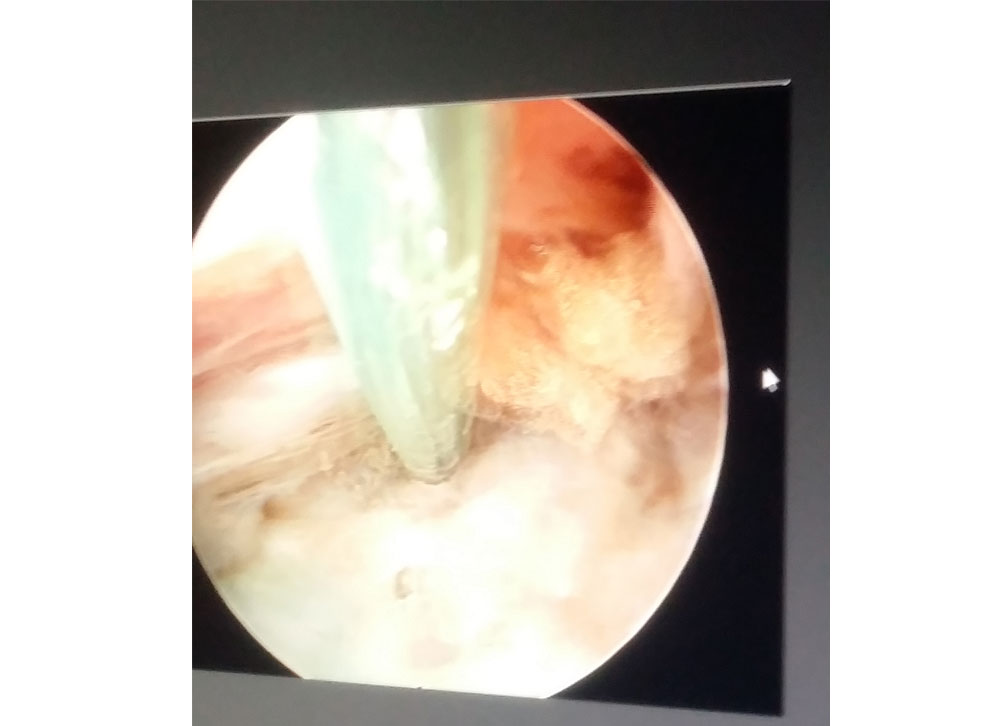

Endoscopic view of spinal canal

Endoscopic surgery in progress